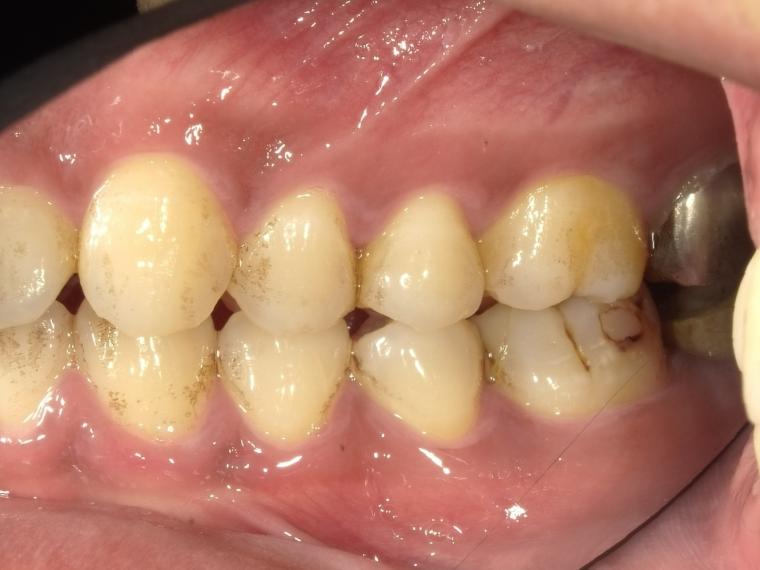

BEFORE

左下第二大臼歯が、残根の状態でご来院された患者さんです。

抜歯後に土台となる骨をつくる処置の後、インプラントを埋入しました。